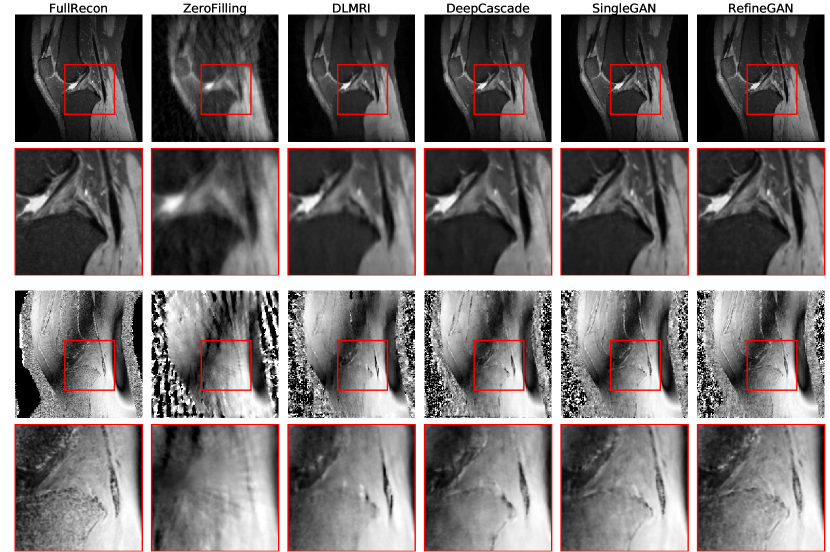

Refer to caption

(a)

(b)

Figure 11: Image quality comparison on the brain (a) and chest dataset (b) at a sampling rate 10% (top 3 rows) and 30% (bottom 3 rows): Reconstruction image, zoom in result and 10×\times error map compared to the full reconstruction.

Image Quality Evaluation: To assess the quality of reconstructed images, we use three image quality metrics, such as Peak-Signal-To-Noise ratio (PSNR), Structural Similarity (SSIM) and Normalized root-mean-square error (NRMSE) Figure 89 and 10 show their PSNRs, SSIMs and NRMSEs error graphs, respectively. Additionally, Figure 11 shows the representative reconstruction of the brain and chest test sets, respectively, using various reconstruction methods at different sampling rates (10% and 30%) and their 10×\times magnified error plots using a jet color map (blue: low, red: high error). Overall, our methods (ReconGAN and RefineGAN) are able to reconstruct images with better PSNRs, SSIMs and NRMSEs. Note that we used the identical generator and discriminator networks (i.e., the same number of neurons) for SingleGAN, and our own method for a fair comparison. We observed that our cyclic loss increases the PSNR by around 1dB, and the refinement network further reduces the error to a similar degree.

By qualitatively comparing the reconstructed results, we found that deep learning-based methods generate more natural images than dictionary-based methods. For example, CSCMRI and DLMRI produce cartoon-like piecewise linear images with sharp edges, which is mostly due to sparsity enforcement. In comparison, our method generates results that are much closer to full reconstructions while edges are still preserved; in addition, noise is significantly reduced. Note also that, comparing to the other CS-MRI methods, our method can generate superior results especially at extremely low sampling rates (as low as 10%, see Figure 11).

Figure 12: Image quality comparison on the knees dataset (top 2 rows: magnitude images, and bottom 2 rows: phase images) at a sampling rate 10% : Reconstruction images and zoom-in results

IV-B Results on complex-valued MRI data

The proposed method can accept 2-channel complex-valued zero-filling image as an input and return a 2-channel complex-valued reconstruction without loss of generality. We used another public database of MR k𝑘k-space 666\urlhttp://mridata.org/fullysampled/knees (referred as the knees dataset) to evaluate our model. This opensource images consists of 20 cases of fully-sampled 3D Fast Spin Echo MR Images. We also chose randomly 10 slices in the middle of each case and further divided them into 2 sets: training and testing, 100 images each. Figure 12 depicts the representative reconstructions of knees test sets at the sampling rates 10% and their 10×\times magnified error plots on the image magnitude (top 3 rows) and phase (bottom 3 rows). As can be seen, the proposed RefineGAN can fruitfully reconstruct the result which has less error compared to other methods.